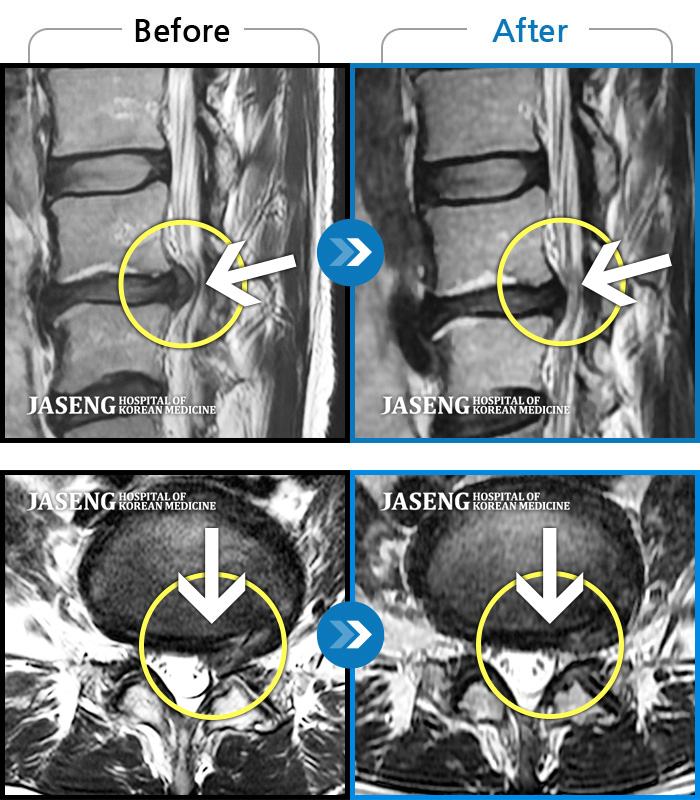

24년 3월 디스크파열 진단받고 극심한 통증으로 입원하여 김재영원장님께 치료받은 후 증상이 매우 호전되어 퇴원한 경험이 있습니다. 원장님께서 퇴원무렵 컨디션 관리를 엄청 당부하셨지만 근무하는 과정에서 발생하는 어쩔수 없는 과로와 극심한 스트레스는 서서이 좋아지던 저의 디스크 통증을 급기야 재발하게 만들었습니다. 7월말 다시 시작된 왼쪽 종아리와 발가락으로 퍼지는 심한 통증과 몸살로 더이상 근무를 계속할수 없어서 급하게 원장님을 뵙고 입원 치료하게 되었습니다. 김재영 원장님께 진료받고 극심했던 방사통이 진통제 없이 생활하기 까지 호전된 경험이 있고 원장님께서도 저의 상황을 어느정도 아시고 계셔서 이번에는 처음 디스크 터졌을때처럼 엄청 겁먹지 않고 원장님께 사소한 증상 하나하나 말씀드리면서 차분하게 치료받을 수 있었습니다. 제가 직장다니면서 힘든 마음으로 다시 입원하게 된 상황을 이해해 주시고 치료가 빠르게 될수 있도록 매일 소소한 증상 하나하나 신경쓰셔서 치료해주시고자 애써 주셔서 진심으로 감사했습니다. 심한 몸살이 디스크 통증과 함께 와서 소화도 안되고 기운도 없이 입원 첫주 무척 힘든 시간을 보냈습니다. 원장님께서는 소화가 잘 되게 침치료도 병행해 주시고, 소화제 종류도 다양하게 바꿔가며 저의 컨디션이 되돌아 올수 있게 처방을 해 주셨습니다. 무수히 많은 환자를 진료하시는 바쁘신 진료시간 중에서도 저의 증상을 매일 편하게 말씀 드릴수 있게 대해 주셔서 소소한 증상까지 말씀 드려 본의 아니게 원장님을 피곤하게 해드렸습니다. 입원 9일차 정도되니 그렇게 아팠던 종아리 통증은 거의 사라지고 소화기능도 조금씩 회복되고 있습니다. 통원치료때도, 입원치료때도 늘 한결같이 저의 증상을 귀담아 들어주시고 치료가 빠르게 될수 있도록 애써 주셔서 고맙습니다. 침 치료시에 어쩔수 없이 듣게 되는 다른 환자분들과 원장님과의 대화속에서도 치료받으시는 어버님 아버님들께서 원장님께 아픈 곳을 편히 말씀하시는것이 느껴졌습니다. 원장님께서도 일일이 다 성의껏 어르신들 말씀 귀담아 들어주시고 치료해 주시는것을 보니 원장님께서는 참으로 인품마저 다정하신 분 같았습니다. 거기에 아픈 통증도 꼭꼭 잡아주시니 원장님께 진료받는 많은 환자들이 원장님의 마음에 심적으로 안정을 받으시고 원장님의 전문적인 의료 도움을 크게 받는것 같습니다. 원장님께서 환자를 대해 주시는 따뜻함, 실력있는 의술 덕분에 제가 입원하는 기간 마음 편하게 치료 받을수 있었습니다. 통증이 자주 재발하면 완치되기가 힘드니 조심해야 된다는 원장님 조언 잘 새겨듣고 올 하반기에는 다시 입원하지 않도록 노력해 보겠습니다. ^^ 원장님께서도 남은 여름 건강 잘 챙기세요~~~ 고맙습니다. 김재영 원장님 ^^

저는 허리디스크 파열로 3월 1일부터 입원하여 3주째 해운대 자생 김재영 원장님께 입원진료를 받고 있습니다.

김재영 원장님께서 혹시 모르니 그래도 MRI를 찍어보고 정확히 원인을 알고 치료를 하자고 권유하셔서 MRI를 찍게 되었습니다. 결과는 디스크 파열로 심각한 상황이었습니다.

저는 수술이 당장 시급한, risk가 상당히 있는 MRI 결과였지만 갑작스러운 결과에 수술을 바로 하기엔 너무 겁이 나서 일단 입원하여 원장님 치료를 받아보기로 마음먹고 바로 입원했습니다.

입원전 한달여간 졍형외과 진통제 복용등으로 저의 통증은 진통제 속에 숨겨져 있었고 입원하여 정형외과 진통제 복용을 중단하자 왼쪽 다리로 뻗어나오는 방사통은 정말 지옥같이 힘들었습니다.

원장님께서 진료해 주시는 추나치료와 약침치료, 오후 병실 침치료, 물리치료 등을 받고 처방해 주시는 자생 한약을 꾸준히 복용했습니다. 야간에 더 심해지는 방사통으로 여러날 새벽을 야간 진료 선생님들 도움 받아가며 힘들게 하루하루를 버티고 있었습니다. 너무 힘들때는 참지 말고 야간 진료 선생님들 도움을 받고 푹 잠자는것이 치료에 더 도움이 될것이라는 말씀도 해주셔서 무조건 참는게 올바른 치료는 아니라는 점도 원장님께 배우게 되었습니다.

지옥같은 1주일이 지나고 아주 조금씩 방사통이 약해지기 시작했고 지금 입원 3주차에 접어들어서는 그렇게 심했던 방사통은 낮에 근무가 가능할 정도로 호전되었습니다.